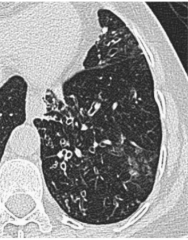

HRCT features of bronchiectasis

(4)

Bronchoartieral ratio >1

Lack of tapering

Airways visible within 1cm costal pleura, or touching mediastinal pleural

Bronchial wall thickening